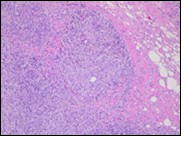

Figure 1.Granulomatous mastitis with the configuration of epitheloid cell granuloma and a lymphoid and plasma cell infiltrate9.

Core needle biopsy of idiopathic granulomatous mastitis enunciates multiple aggregates of non- caseating epitheloid cell granulomas within and encompassing breast lobules, constituted of epitheloid histiocytes, lymphocytes, neutrophils and multinucleated giant cells. Granulomatous inflammation is predominantly lobulo-centric. The inflammation is preponderantly composed of lymphocytes, plasma cells, epitheloid histiocytes, multinucleated giant cells and neutrophils. Neutrophils can configure micro-abscesses and encompass vacant micro-cystic cavities, morphological features which are in common with cystic neutrophilic granulomatous mastitis. Non specific lobulitis along with a lymphoid and plasma cell infiltrate accompanies the granulomatous inflammation. Necrosis is usually absent. Neutrophilic micro-abscesses can be accompanied by fistula formation 4, 5.

Multinucleated giant cells are detected in an estimated three fourths (78.5%) instances. Plasma cells are discernible in around half (53.9%) of the subjects and usually appear at the margins of cystic vacuoles with centric accumulation of neutrophils within the granulomas.